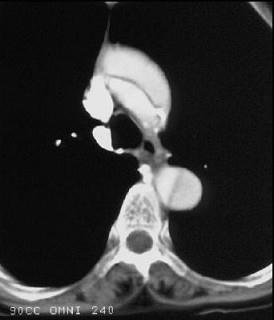

问题 男,64岁,突感胸部剧痛2h,呈撕裂样,并向背部放射,有高血压病史10年,含服硝酸甘油3片不能缓解,CT检查如图所示。首先应考虑的诊断是 ( )

选项 A、急性胸膜炎 B、急性心肌梗死 C、急性胆囊炎 D、急性胰腺炎 E、主动脉夹层

答案 E